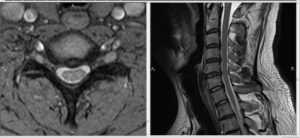

МРТ шейного отдела позвоночника: показания к проведению

В области шеи сосредоточено большое количество структур, связанных с ЦНС и другими анатомическими элементами человеческого тела. Патологии, развивающиеся в этой области, несут угрозу для жизни пациента. Плотное расположение шеи затрудняет диагностику местных заболеваний — рутинными методами зачастую не удается выявить проблему. Поэтому в большинстве случаев рекомендуется проводить МРТ шеи при необходимости детальной диагностики. Когда необходимо …